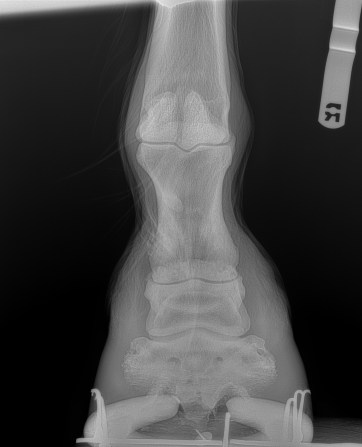

Yesterday, we took our paint horse Cody to the vet clinic for his routine therapeutic shoeing appointment which periodically involves x-rays to see how he’s progressing. Cody has “ringbone” which is a horse person’s term for osteoarthritis. In Cody’s case, as the x-rays revealed yesterday, he has both high and low ringbone, which means the arthritis affects the coffin joint and the pastern. Which means, for Cody, things hurt. His new shoeing prescription should help, as will the injections of steroids he will soon receive.